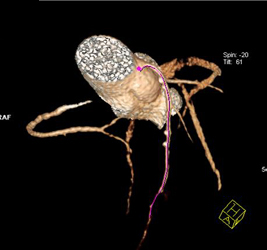

Left Main Arises Off Right Coronary Artery